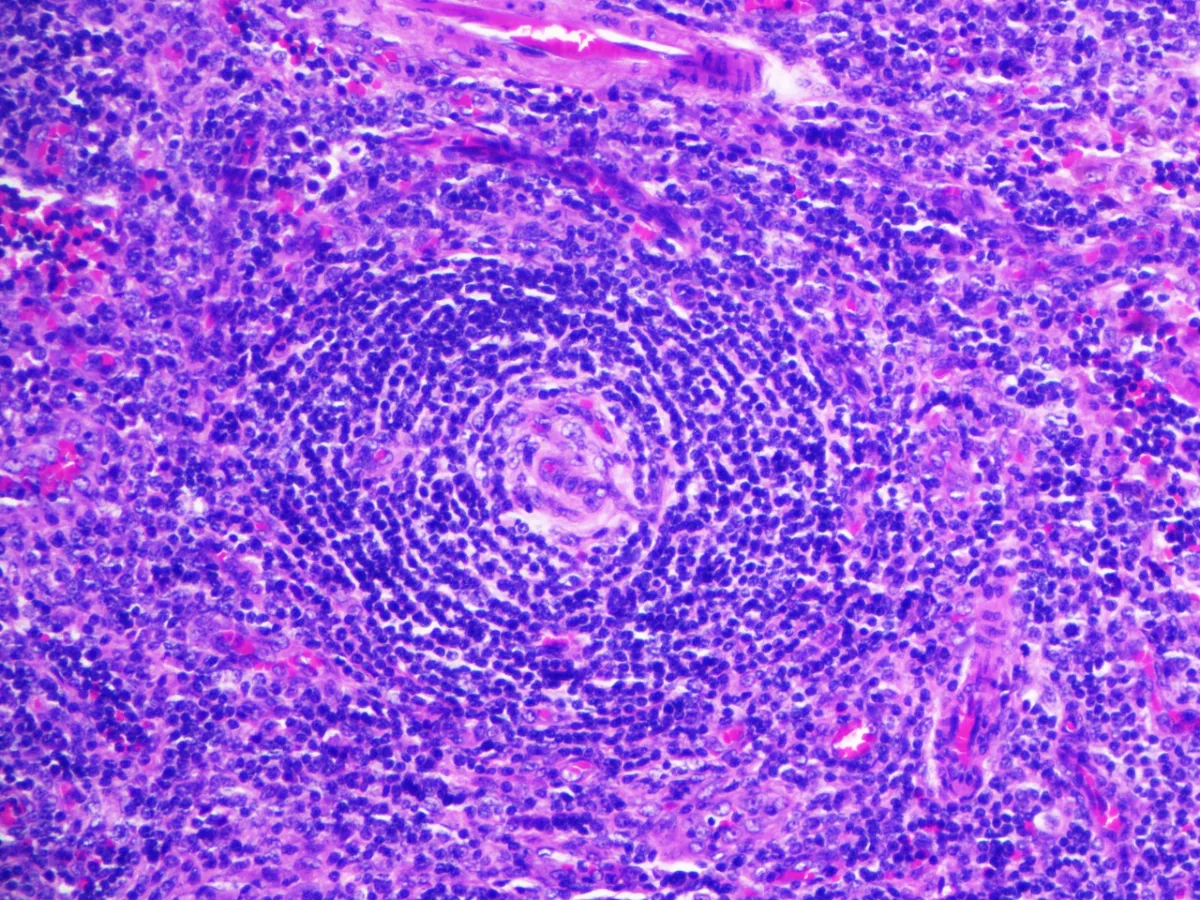

Diagnóstico: Enfermedad de Castleman, variante hialino-vascular.

- La variante hialino-vascular es la más frecuente en la EC unicéntrica, y se caracteriza por una hiperplasia linfoide con centros germinales regresivos y zona del manto expandida en aspecto “en capas de cebolla”. Se acompaña de proliferación vascular en forma de vénulas con endotelio alto, y células dendríticas foliculares prominentes (PMID: 35997567).

- En el estudio citológico de la EC se observa proliferación de vasos asociados a centros germinales (PMID: 18855889).